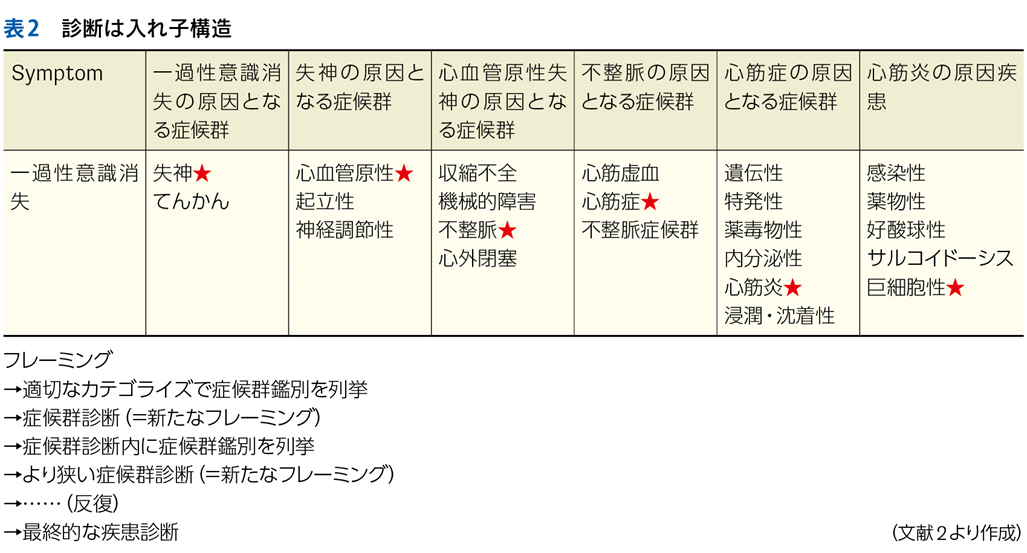

▶ 診断はいわば「入れ子構造」であり,症候群の診断がその原因となっている症候群の診断を呼び,またその原因症候群の診断を呼び……というように,診断プロセスが繰り返され,そのたびにフレームが狭まって,最終的な診断に行きつく。

▶ 表2はNew England Journal of Medicine誌のClinical Problem Solvingに掲載されたケース2)に少し変更を加えてそのプロセスを示したものだが,ここでは「一過性意識消失」という症候からスタートして症候群診断(表中の★)を反復して最終診断に至っている。